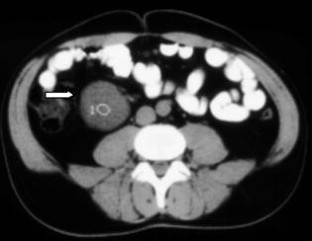

Wir berichten über das diagnostische und therapeutische Vorgehen anhand von 7 Patienten mit Blutungen aus der A. gastroduodenalis (n=5) nach pankreaschirurgischen Interventionen bei Pankreaskopfkarzinom, Rezidiv eines Liposarkoms und chronischer Pankreatitis, der A. hepatica communis (n=1) bei chronischer Pankreatitis und der A. mesenterica superior (n=1) nach akuter Pankreatitis. Anhand von 4 Kasuistiken werden unsere Erfahrungen mit der Implantation von Stentgrafts (Hemobahn®-Prothesen) vermittelt. Den Vorteil der Stentgrafts sehen wir in der sofortigen Blutstillung bei fehlendem Kontakt der Endoprothese zu infiziertem Gewebe und Erhalt der Perfusion des abhängigen Organs. Unsere positiven Erfahrungen mit diesen interventionellen Therapieverfahren erfordern jedoch weitere klinische Untersuchungen, wobei im Mittelpunkt die Indikationen, die technische Erfolgsrate, die stentbedingten Komplikationen und die Langzeitverläufe stehen sollten.

Spontaneous or postoperative hemorrhage into the abdominal cavity due to inflammatory vessel arrosion represents an uncommon but menacing situation. According to the literature, such hemorrhage is associated with a lethality of nearly 2%. Therapeutical options include reoperation and interventional radiological techniques such as endovascular catheter techniques with stent graft implantation or the embolization of vessels. We report on the management of seven cases with hemorrhage either from the gastroduodenal artery (n=5) following pancreatic surgery for pancreatic carcinoma, liposarcoma, and chronic pancreatitis or from the common hepatic artery (n=1) and the superior mesenteric artery (n=1) following chronic pancreatitis. The present article describes our experiences with stent graft implantation (hemobahn prosthesis) in four cases. Based on these experiences, we see the advantages of stent grafts in primary hemostasis without any contact to infected tissue and the preservation of regular perfusion. However, further clinical data are required focussing on indication, technical success rates, stent-related complications, and long-term outcome.